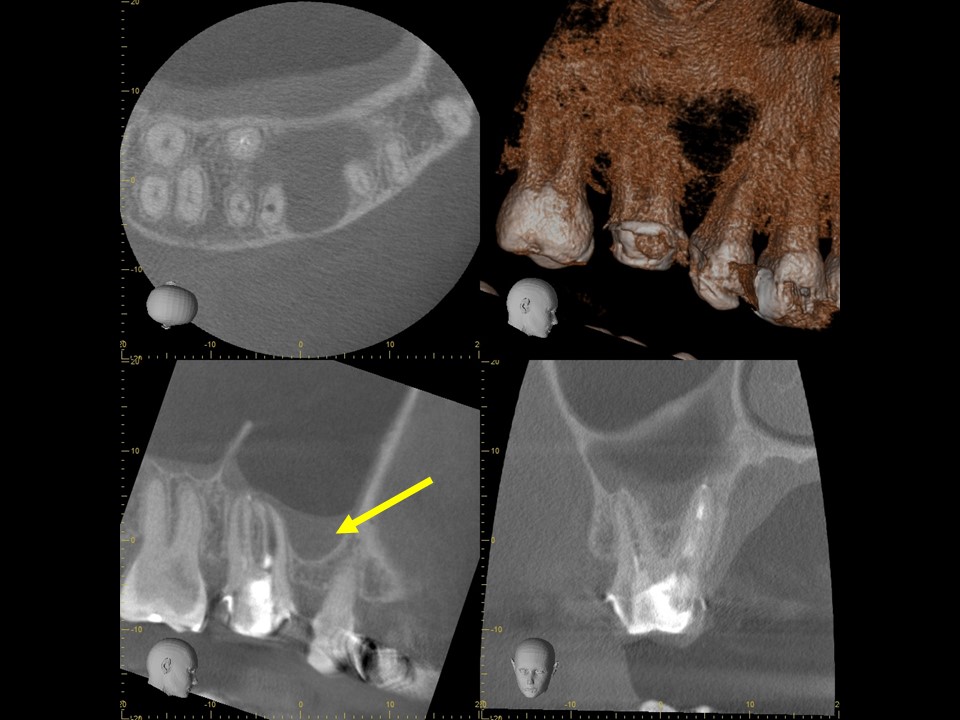

同CT画像。上顎洞のX線不透過部は消失し、上顎洞炎が治癒しているのが分かる。